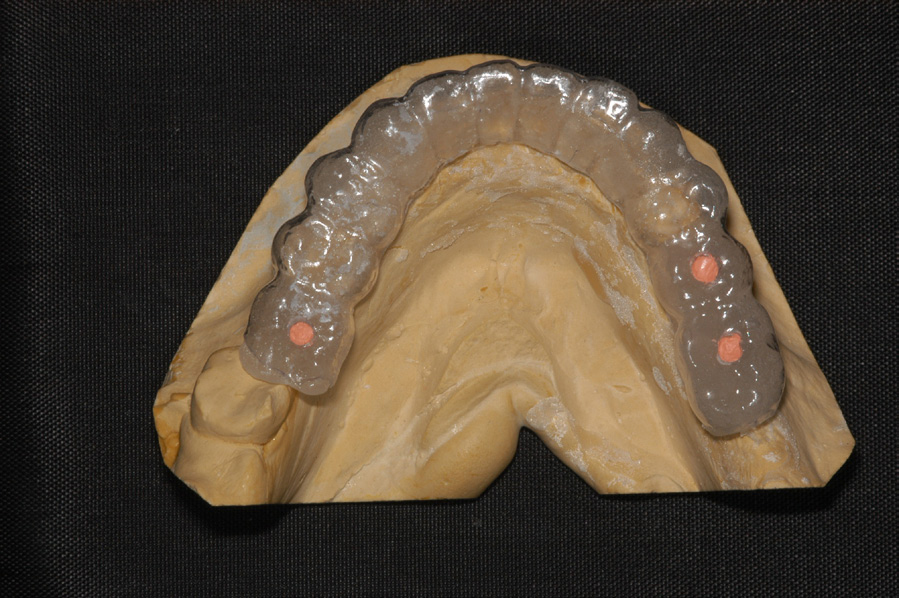

DIAGNOSTICS

A few records are necessary to determine the treatment options for the patient and placement of the implant(s). When considering potential implant treatment, the standard of care today is for the patient to receive a computed tomography (CT) scan. The patient should wear a radiographic guide during the scanning procedure. This radiographic guide is a great communication tool to help the surgeon visualize implant placement (Figure 25). To make the radiographic guide, maxillary and mandibular mounted impressions need to be obtained to determine the correct bite and location of the teeth to be replaced with implants. The guide is prescribed and made in a dental laboratory.